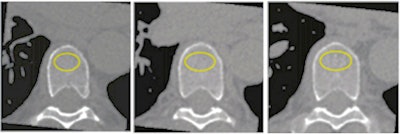

A participant's noncontrast-enhanced axial CT with volume of interest (yellow circles) in the trabecular bone compartment of three vertebrae for bone mineral density measurements. Images and caption courtesy of the RSNA."We believe that opportunistic BMD testing using routine CT scans can be done with little change to normal clinical practice and with the benefit of identifying individuals with a greater fracture rate," Therkildsen said.